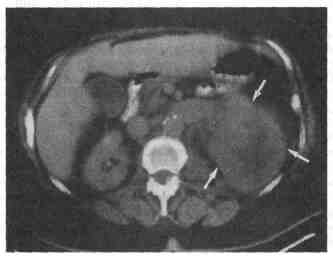

следует выполнить до и после внутривенного введения контрастного вещества.

Рис. 6-1. КГ опухоли левой почки. 9. Эффективно ли применение КТ при определении стадии рака предстательной железы? Значение применения КТ для определения стадии рака предстательной железы невелико. Метастазы в тазовые лимфоузлы трудно поддаются визуализации. Различия между раком и нормальной тканью предстательной железы при небольших размерах поражений неотчетливы. Раковое образование можно определить только на далеко зашедших стадиях, при его прорастании за пределы предстательной железы в основание мочевого пузыря или семенные пузырьки. Для определения стадии рака предстательной железы при обычном обследовании применять КТ не следует. 10. В какую область урологии КТ вносит наиболее существенный вклад? Применение КТ вносит наиболее существенный